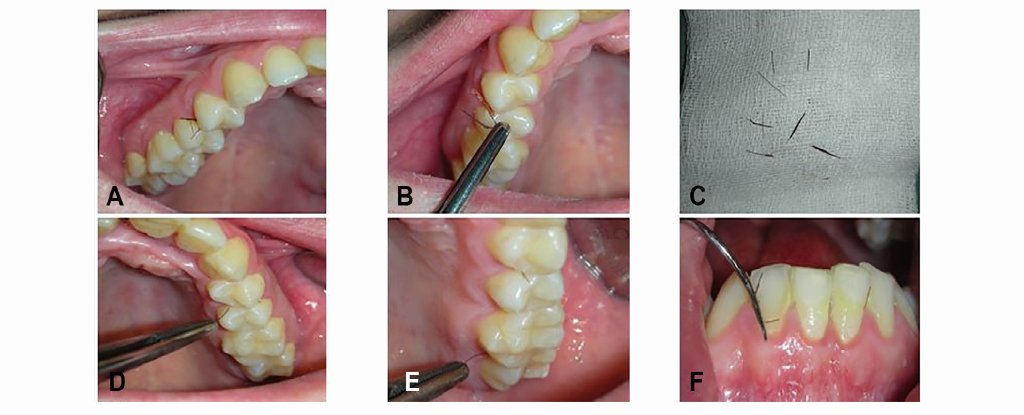

У итальянки выросли волосы на деснах

В Италии девушка обратилась к врачам с жалобами на волосы, растущие на деснах. О необычной пациентке врачи рассказали в статье в журнале Oral Surgery, Oral Medicine, Oral Pathology, Oral Radiology.

Впервые девушка пришла к врачам в 2009 году, в то время у нее на небе росли несколько волосков, похожих на ресницы. Изучив научную литературу, врачи нашли всего пять таких случаев, все они наблюдались у мужчин. Из-за редкости заболевания установить его причину оказалось сложно. У пациентки оказался синдром поликистозных яичников, который часто сопряжен с избытком волос на лице и теле. Вряд ли он вызвал рост волос на слизистой рта, но наверняка подстегнул это состояние, решили врачи. Они удалили волосы хирургически, а девушке назначили гормональные препараты.

Это помогло на какое-то время, однако спустя годы пациентка забросила лечение, и волосы появились вновь. Теперь их стало больше. На этот раз врачи не только их удалили, но и взяли образцы тканей десен для анализа. Они не берутся сказать наверняка, но подозревают, что все дело в формировании тканей в период развития эмбриона. Слизистая рта в это время мало чем отличается от остальной кожи, и, теоретически, там тоже могут образоваться волосяные фолликулы.

Врачи не сообщают, начала ли пациентка вновь принимать лекарства. Также неясно, влияет ли ее аномалия на здоровье и приносит ли какой-либо дискомофорт.